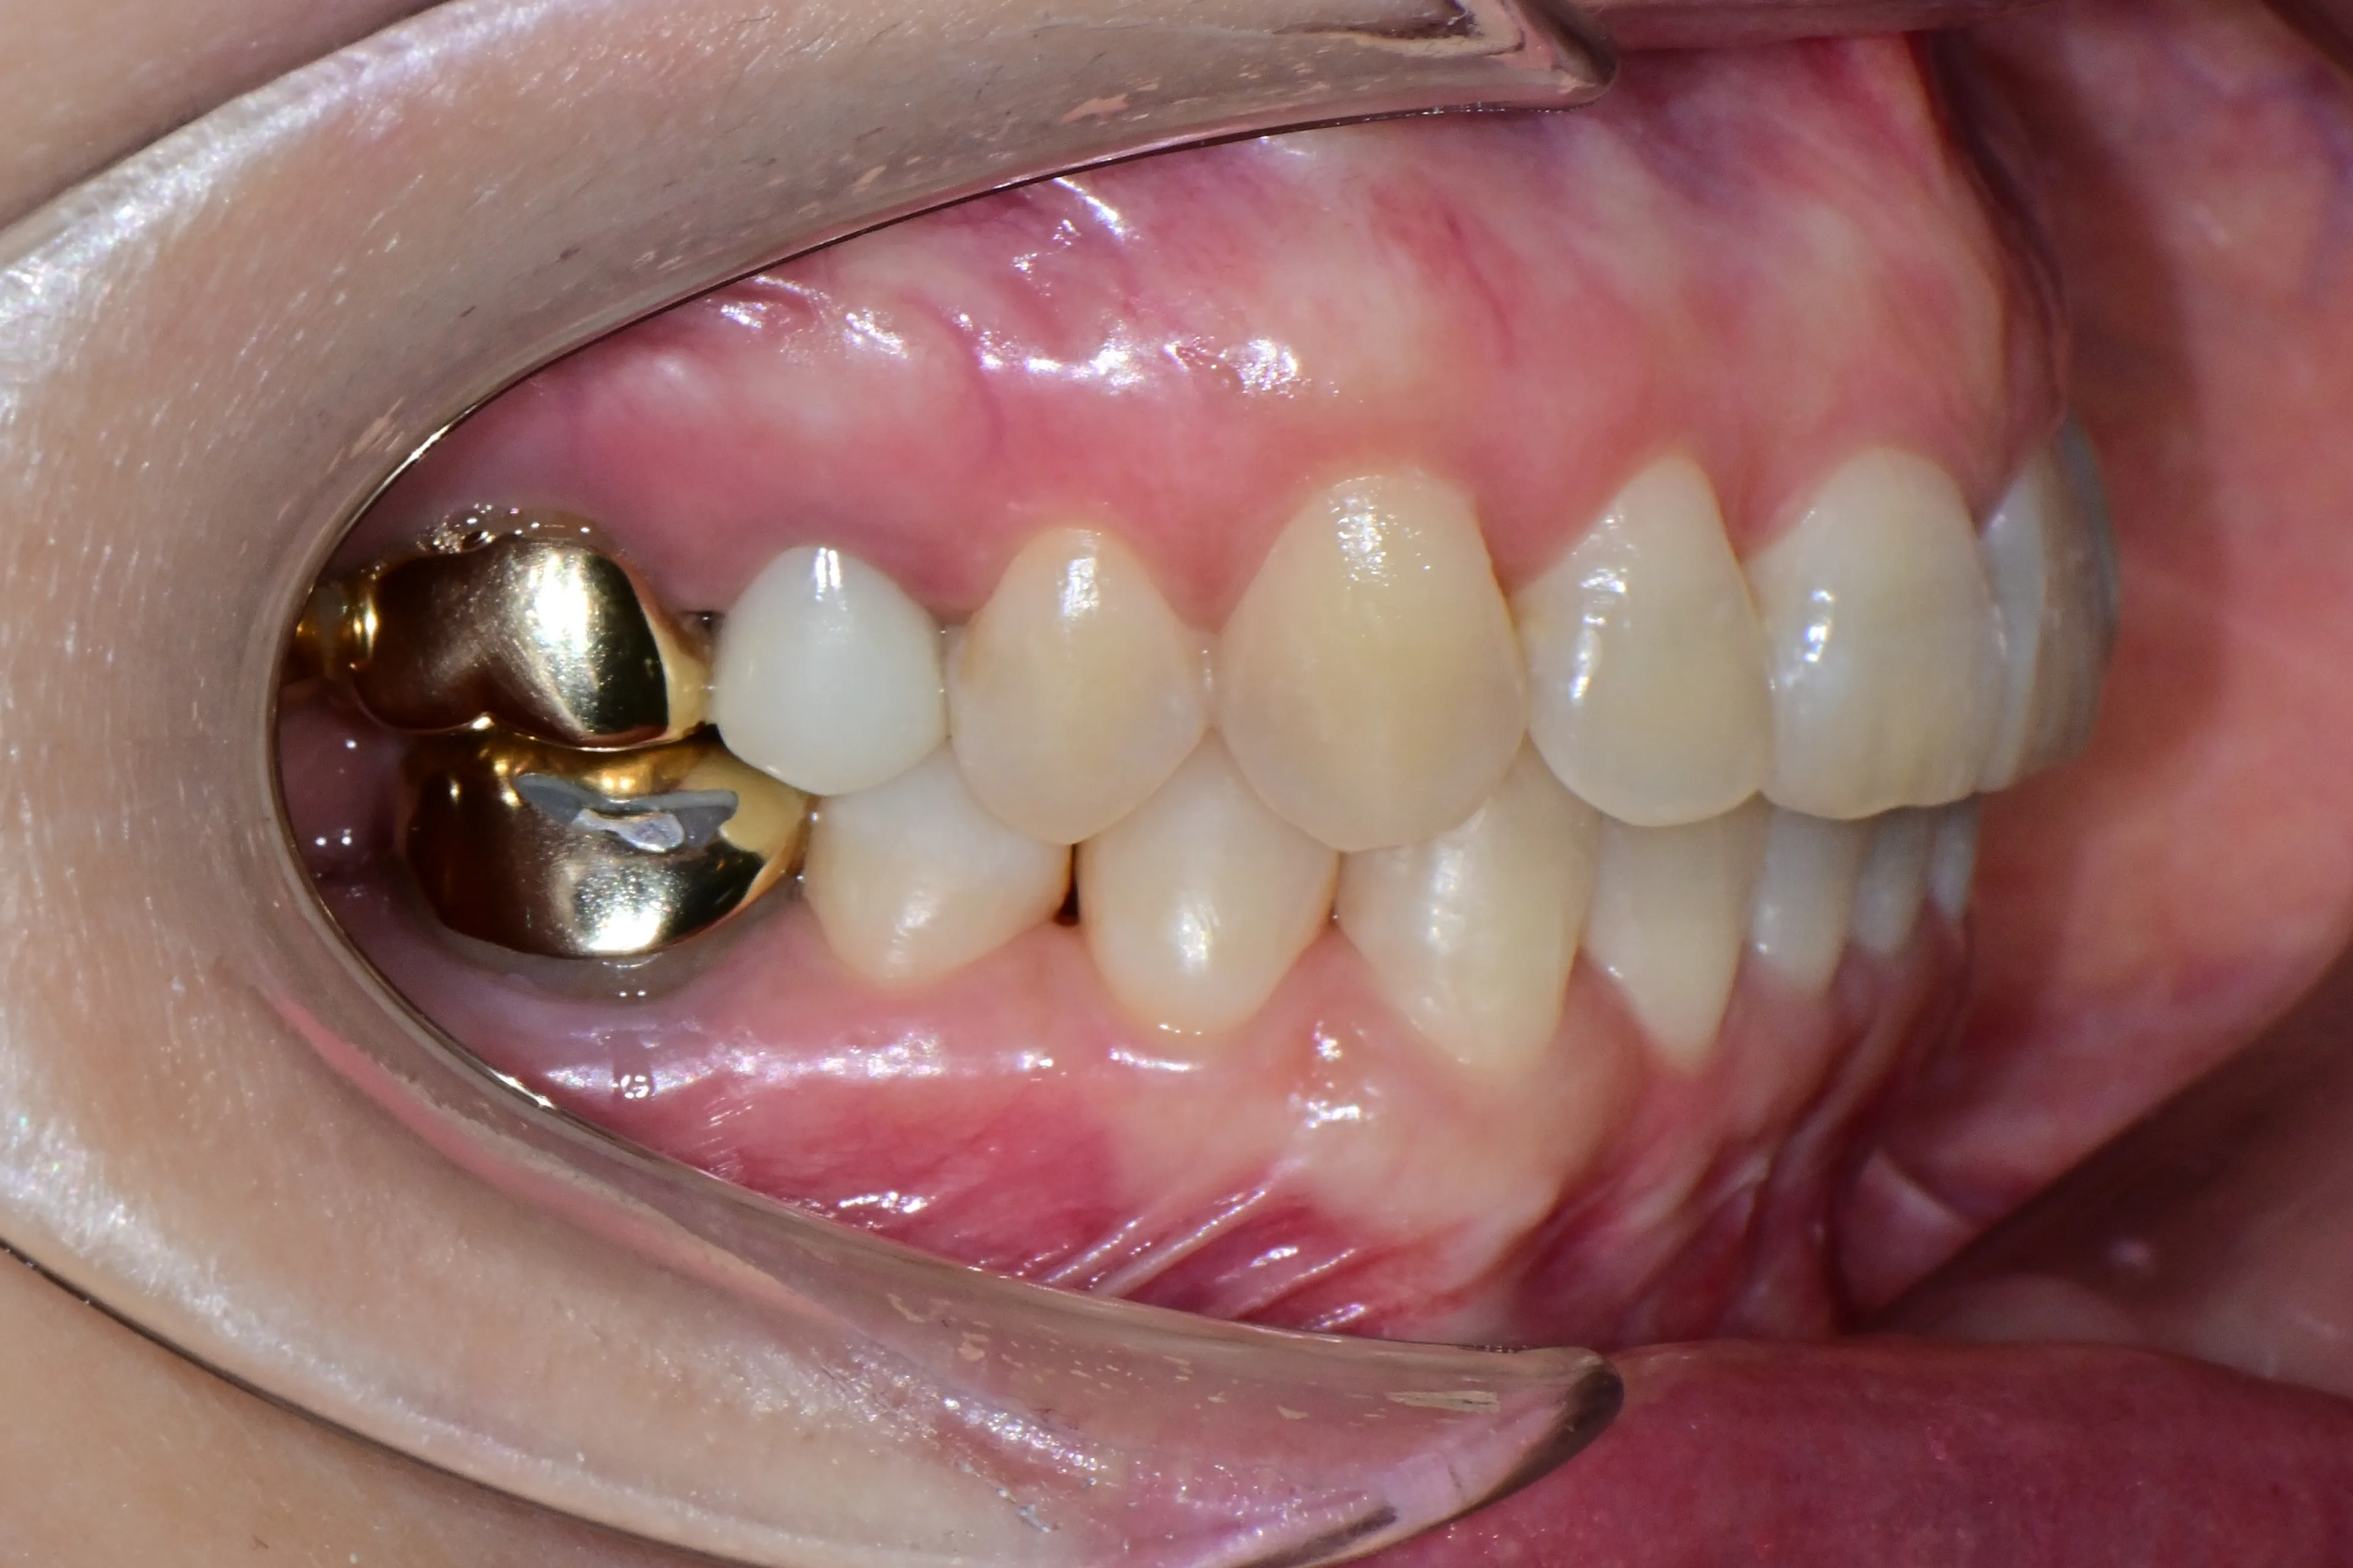

이 환자분은 이미 구강 안에 여러 개의 임플란트와 브릿지 보철물이 있는 상태였습니다. 앞니는 가지런하지 않고, 윗니가 아랫니를 깊게 덮는 과개교합(deepbite)도 있었습니다. 이런 경우 가장 중요한 것은 기존 임플란트와 보철물의 교합을 그대로 유지하면서, 나머지 치아만 가지런하게 배열하는 것입니다.

인비절라인의 디지털 치료 계획을 활용해서, 임플란트와 보철물이 있는 어금니는 움직이지 않도록 고정하고 앞니 위주로만 이동시켰습니다. 덕분에 발치 없이, 고무줄이나 미니스크류 같은 추가 장치 없이도 15개월 만에 치료를 마무리할 수 있었습니다.

보철물이나 임플란트가 많다고 교정이 어려운 것은 아닙니다. 오히려 이를 고정원으로 활용하면 치료 효율이 높아지는 경우도 있습니다.